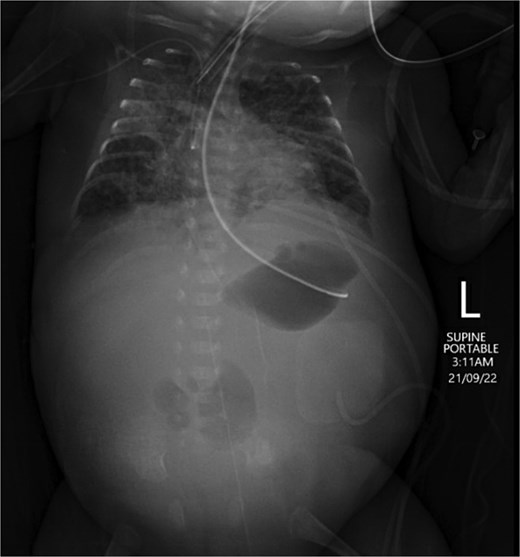

On Day 17, abdominal examination was benign, and the general condition of the baby was stable; therefore, feeding was recommenced and increased gradually. The baby tolerated up to 120 ml/kg feeds and had multiple changing stools. On Day 25, the baby demonstrated abdominal distension and increased inflammatory markers. Feeding was stopped, and antibiotics restarted. The baby, however, continued to deteriorate, with increasing abdominal distension, and started to have bilious vomiting with no stools for 4 days. An ultrasound scan showed no collection, an echogenic liver, and minimal free fluid in the left side of the abdomen. An abdominal X-ray showed a relatively gasless abdomen, concerning for necrotic bowel (Fig. 2). Therefore, laparotomy was performed on Day 29.

Abdominal X-ray on Day 25 demonstrating a gasless abdomen concerning for necrotic bowel.